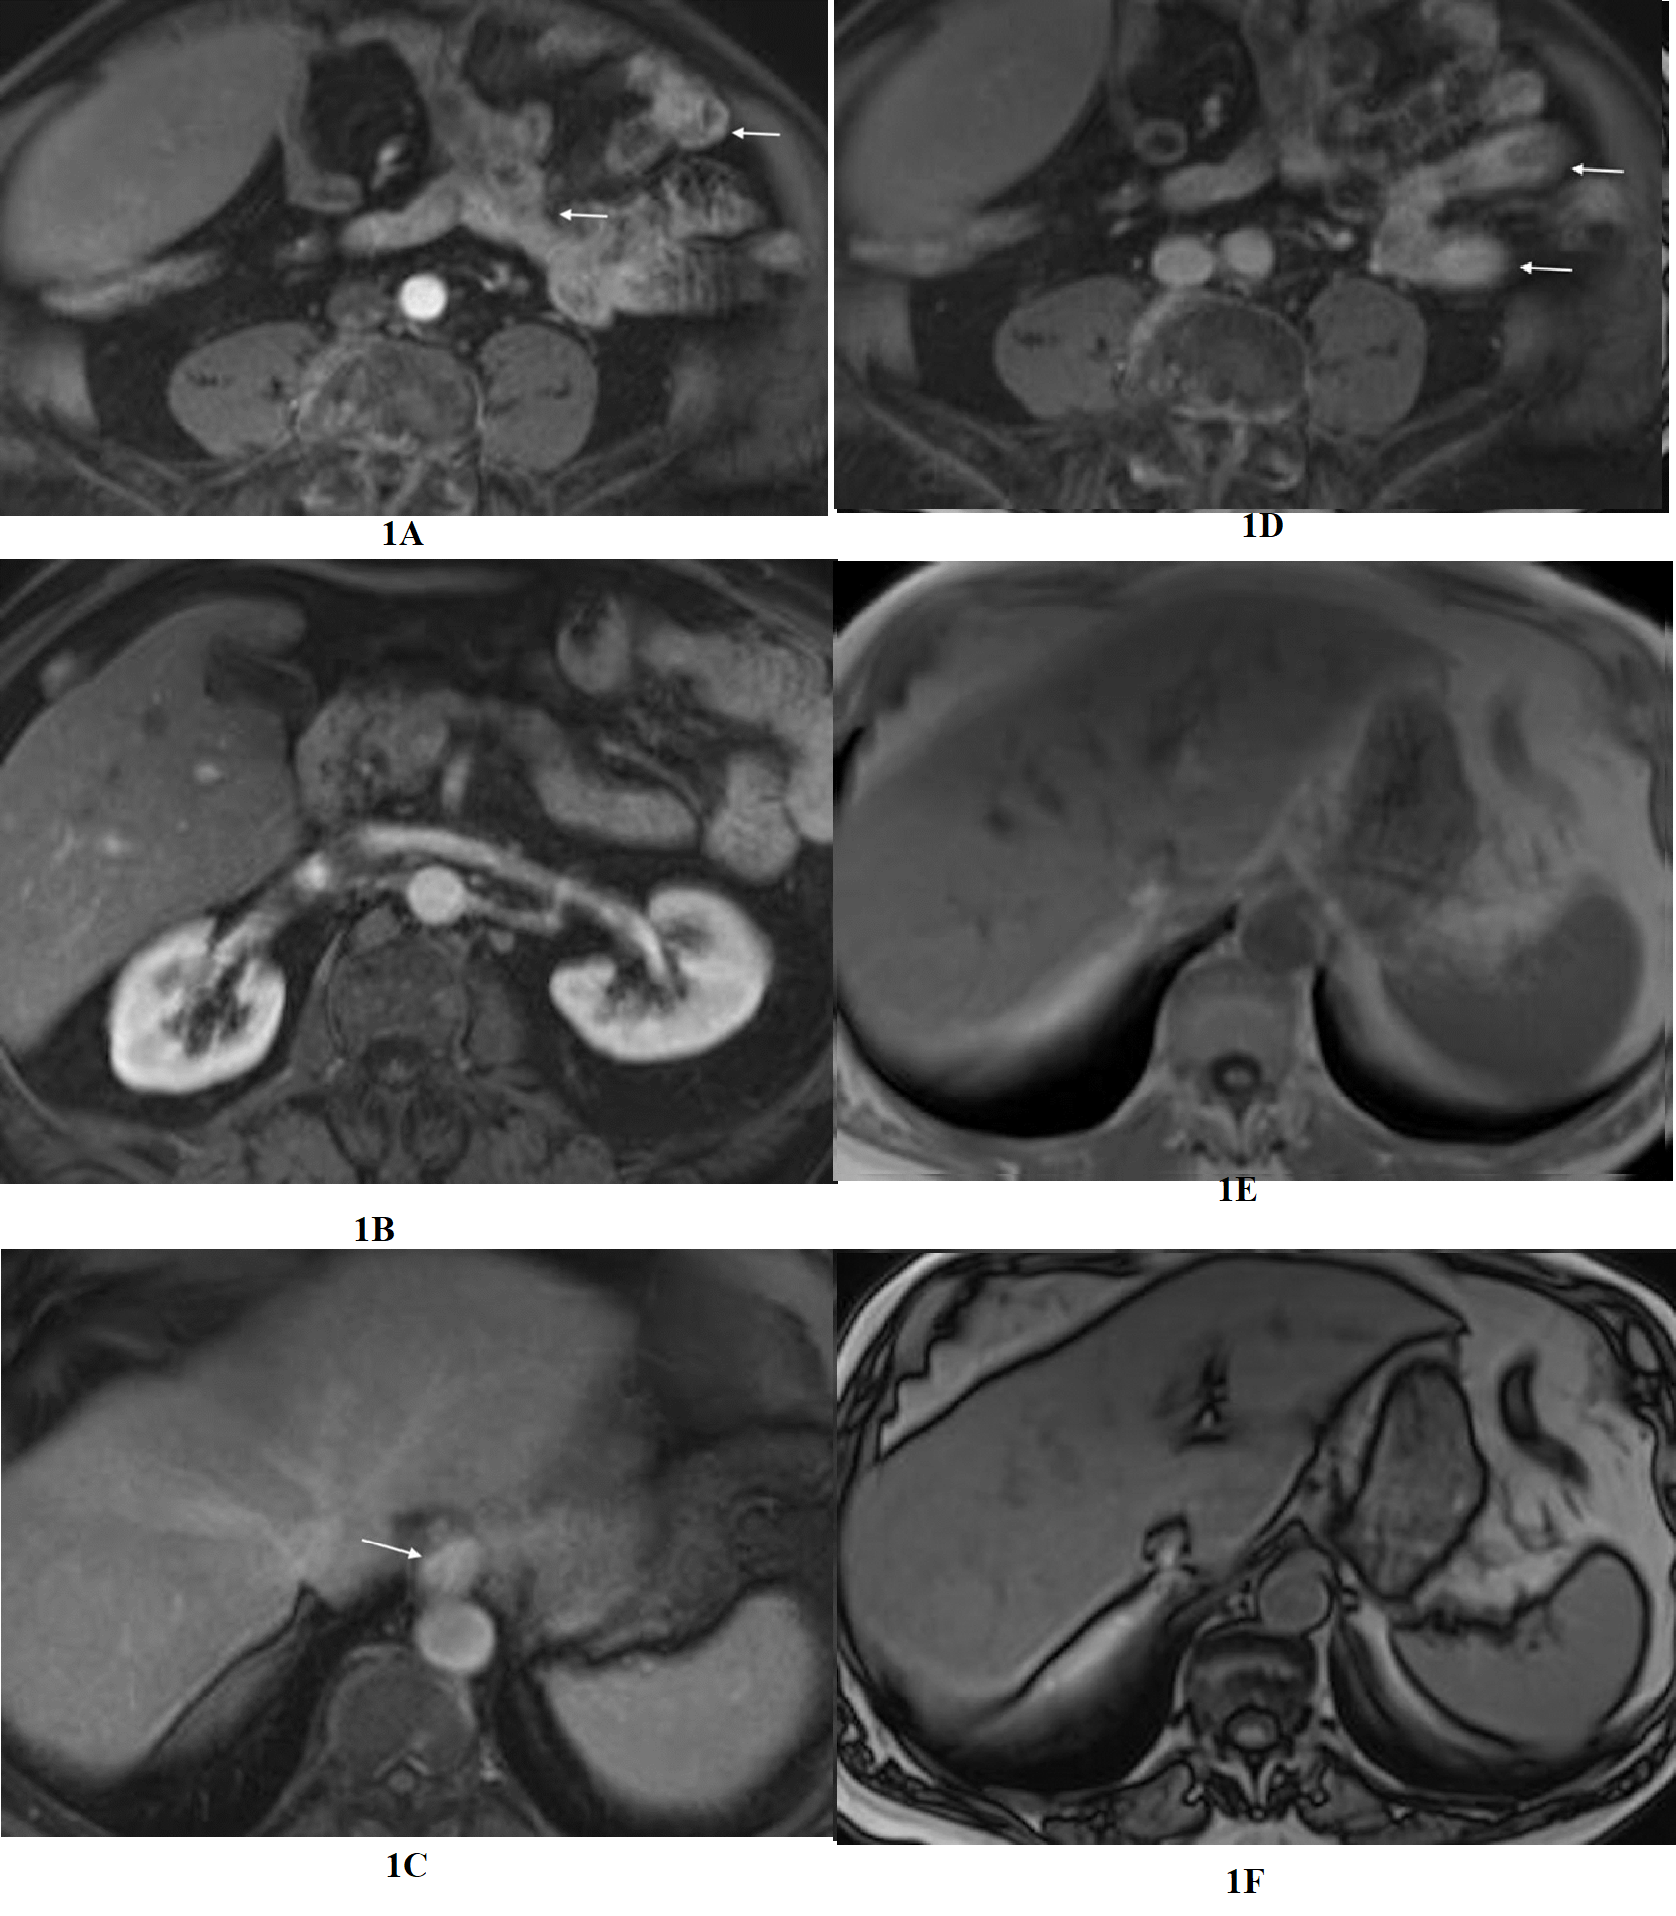

In the preliminary study, among 100 patients with hepatosteatosis, there were 59 Females (all patient-mean aged 52.6 years and an age range of 19-65). The presenting complaint was abdominal pain, right upper quadrant, or general pain in 77 (65 presented with generalized abdominal pain, 10 with right upper quadrant (RUQ) pain, and 2 with left upper (LUQ) pain). Ninety-nine patients showed increased enhancement of the upper GI tract in at least one segment (esophagus and duodenum most commonly). The central observation was that increased upper GI enhancement of some combination of distal esophagus, distal stomach, proximal duodenum, and jejunum was essentially always present in the setting of hepatosteatosis, observed in 99/100 reported cases (Figure 1) (Table 1).

Figure 1 Evaluation of the upper abdomen of a patient with clinical diagnosis of irritable bowel syndrome. Axial T1-weighted images acquired in the arterial phase (a,b) and the interstitial phase (c,d). Moderate severity increased enhancement of the distal esophagus is appreciated in the interstitial phase (arrow, c). Duodenal inflammation is also depicted with increased enhancement in the interstitial phase (arrow, d). The enhancement approximates the intensity of adjacent IVC and aorta. Increased esophageal enhancement is most easily appreciated of all the upper GI segments, likely due to its fixed and consistent location. In-phase (e) and out-of-phase (f) images of the liver, exhibit normal signal relationship of liver and spleen on in-phase, but on out-of-phase signal of liver and spleen are approximately the same, which reflect mild hepatosteatosis.